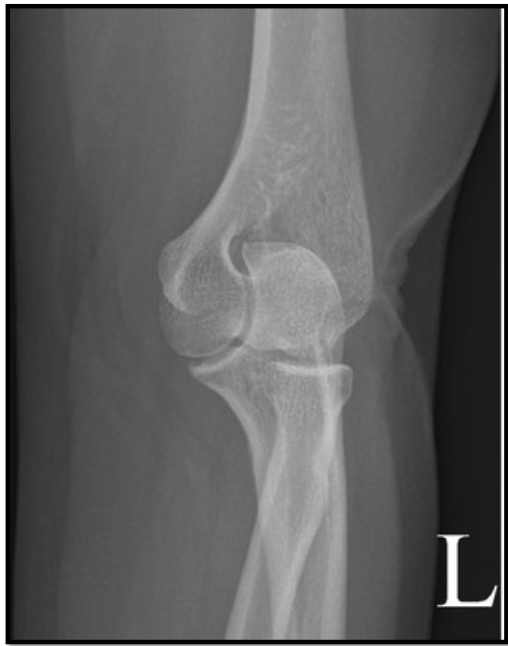

Lateral Elbow Criteria

• elbow flexed 90

• capitulum and trochlea superimposed

• articulating surfaces of the radial head and coronoid process are aligned